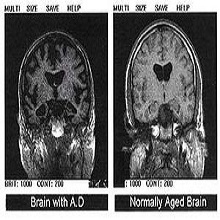

Алцхајмерова болест (АБ) дефинисана је као клиничко-патолошки ентитет који најчешће има амнестичку презентацију (почиње поремећајима памћења, а праћен је развојем прогресивне деменције у следећих неколико година). |